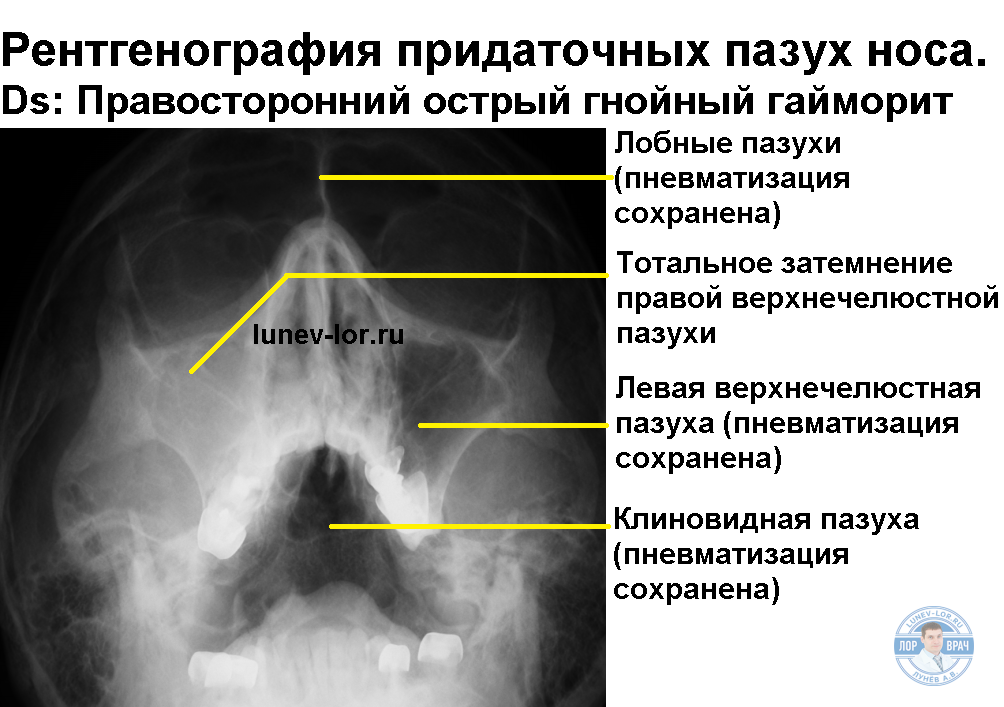

КТ-снимки хронического этмоидита: подробная визуализация

Раздел: Фотодневник открытий